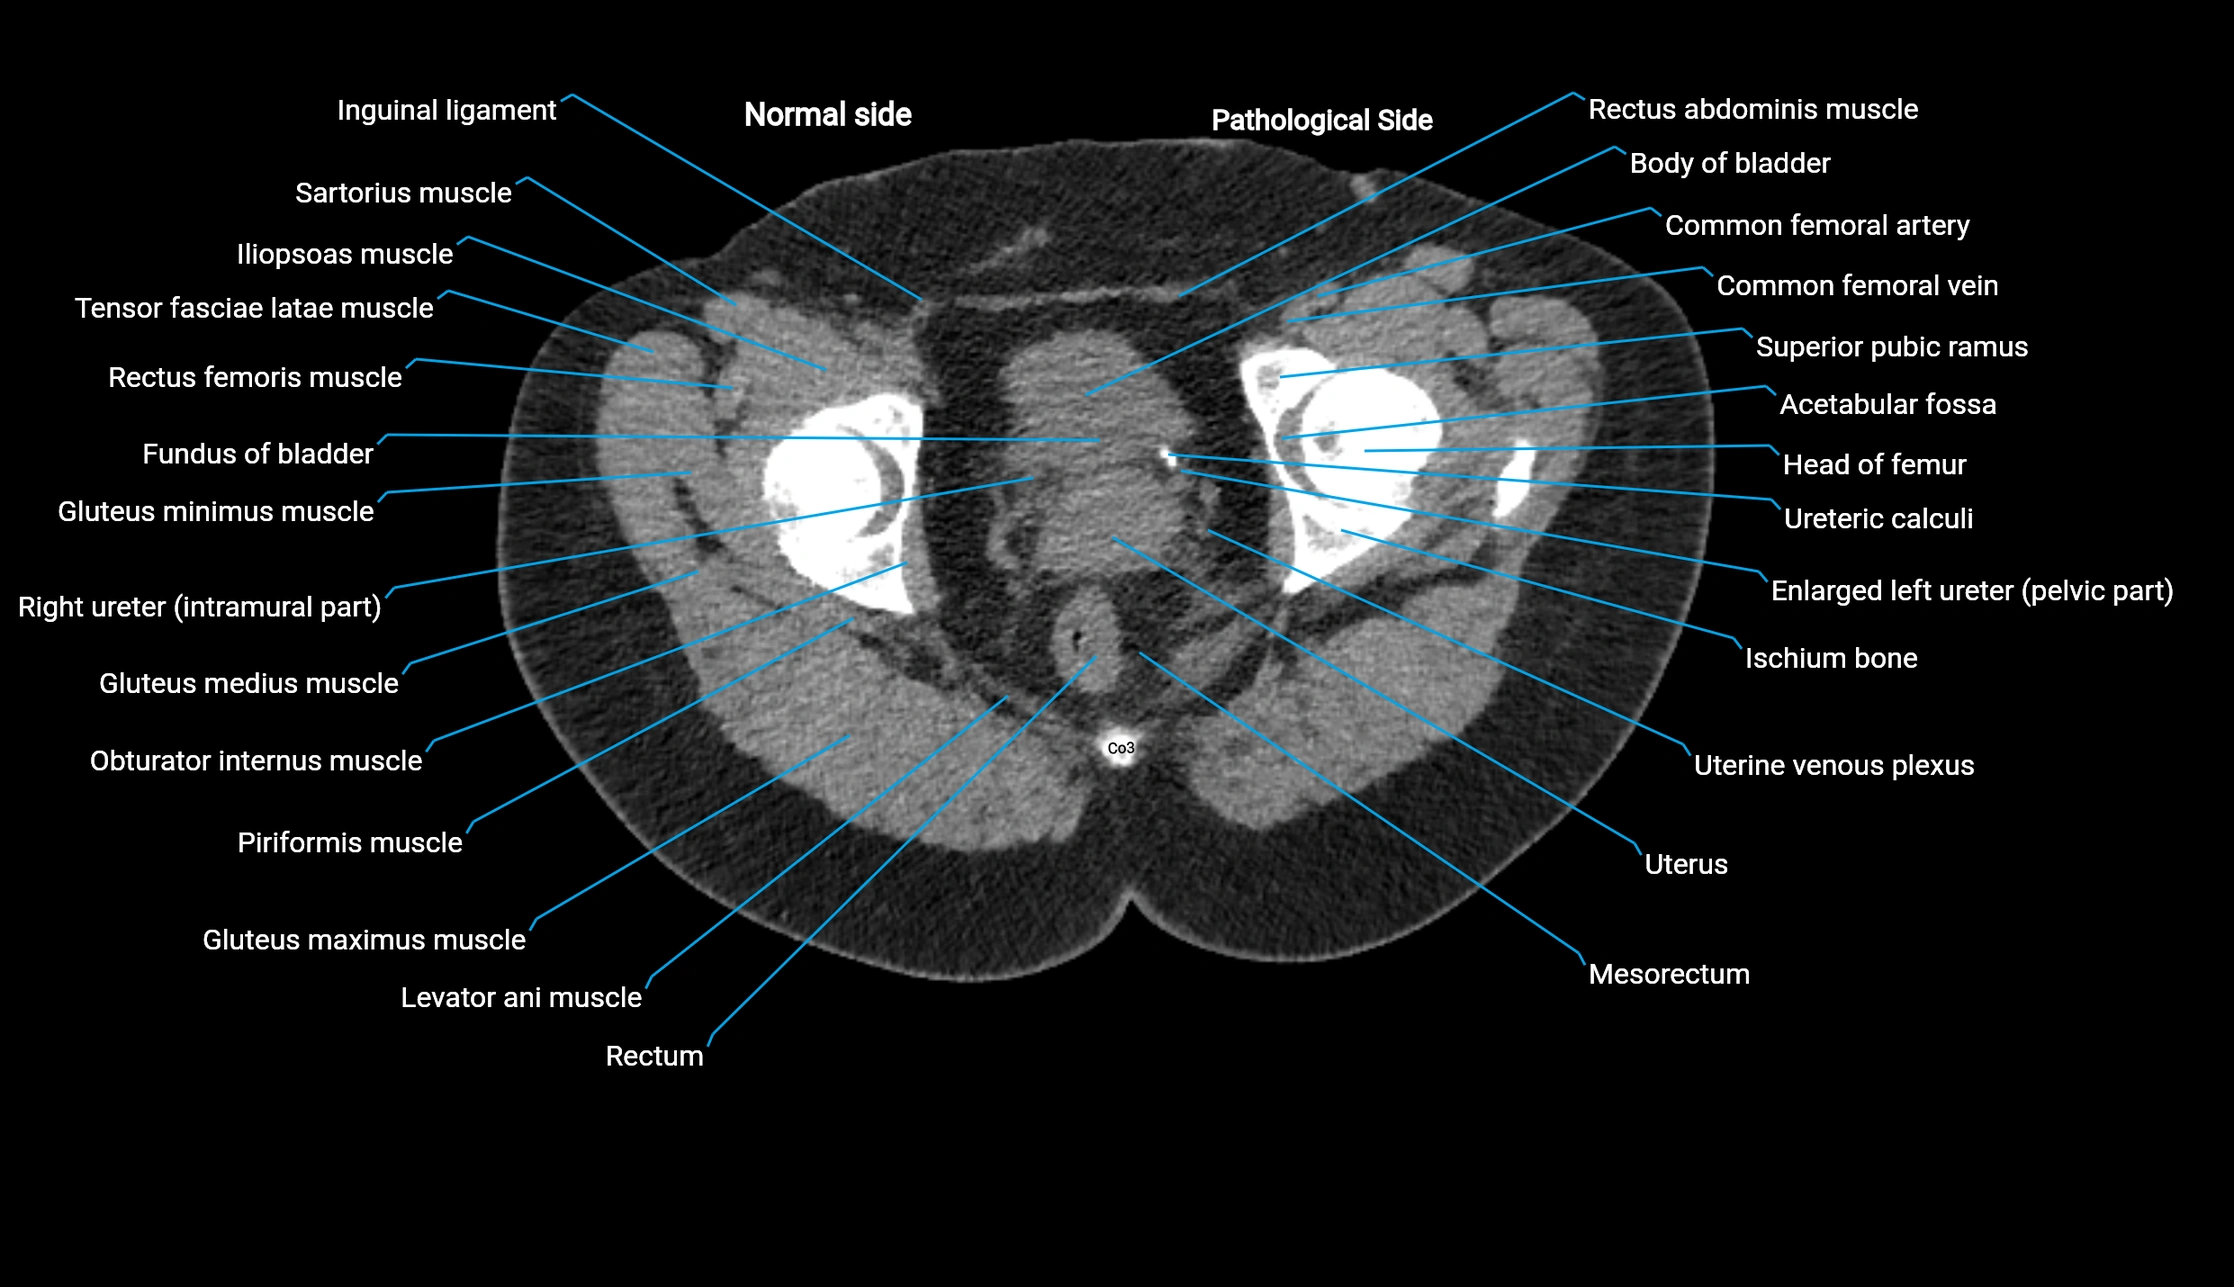

CT image

image